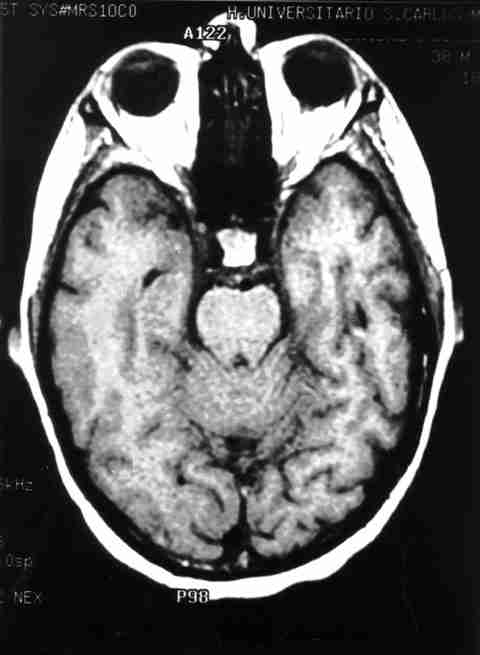

Figura 4

RMN EN T1. REALCE Y ENGROSAMIENTO MENÍNGEO EN ZONA PARIETO-TEMPORAL DERECHA Y PARTE SUPERIOR DE VERMIS.